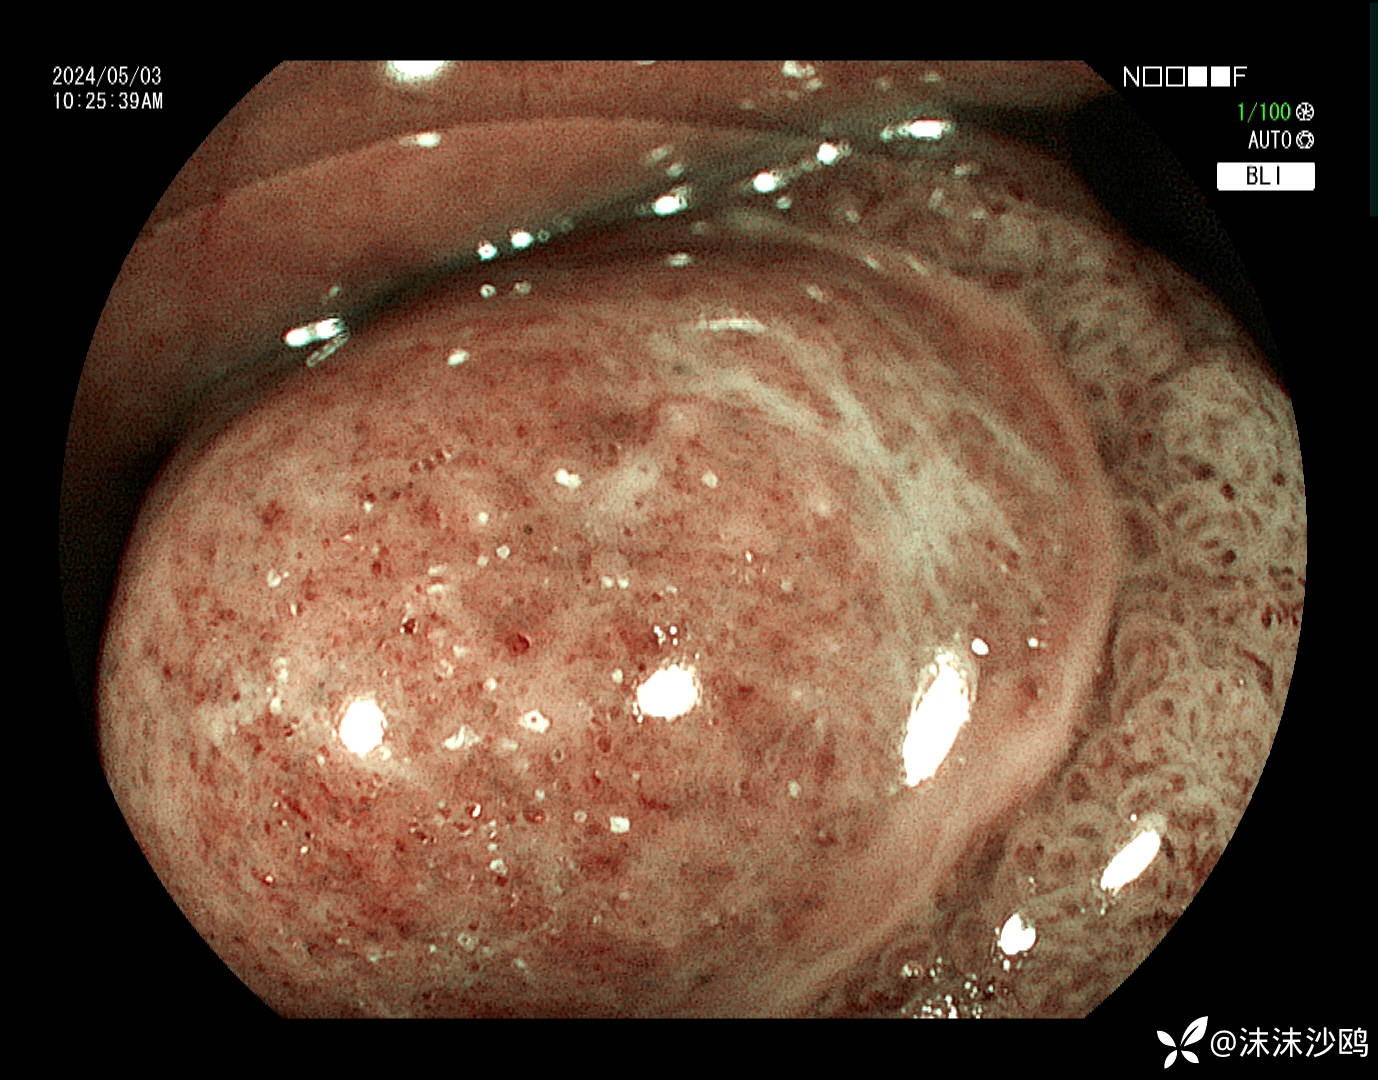

BLI

BLI+ ME

边缘的表面结构呈脑回状